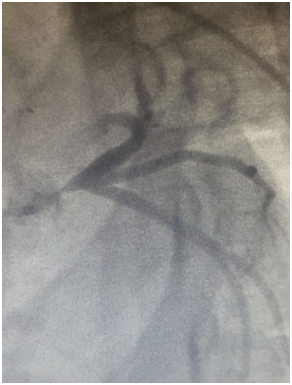

She was admitted to the emergency department. She reported a chronic fatigue and claudications of the upper limbs. The physical examination showed a significant asymmetry in pulses and blood pressure between right and left limb. All right pulses were absent with souffle on right subclaviar artery her blood pressure was 80/40mmhg in the right arm and very high in the left arm. The 12 lead electrocardiogram showed sinus tachycardia at 130bpm and diffuse repolarization abnormalities, ST-segment depression of 2-5mm in anterior, septal, apical and lateral derivations, and T-wave inversion in lateral derivations. As the diagnosis of non ST elevation myocardial infarction was made, the patient was referred to the cardiological department. Coronary angiography (Figure 1) revealed a severe stenosis (70-90%), 16-20mm of length of the left main coronary artery. There were no lesions in the other coronary arteries. The 2-dimensional transthoracic echocardiography showed an impaired left systolic function, regional wall-motion abnormalities , with a left ejection fraction of 0.35,high filling pressure, secondary pulmonary hypertension in addition to a moderate mitral regurgitation ,a moderate aortic regurgitation, and a good right systolic function.

Figure 1 Coronary angiography: Left main coronary severe stenosis.